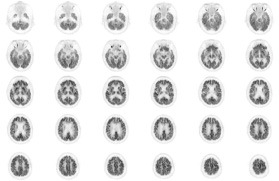

Head / Case2 : FDG

Axial

Courtesy : Kindai University Hospital

- Imaging protocol

- Injected dose: 3.29 MBq/kg, 18F-FDG

- Uptake time: 38 minutes

- Scan time: 30 minutes